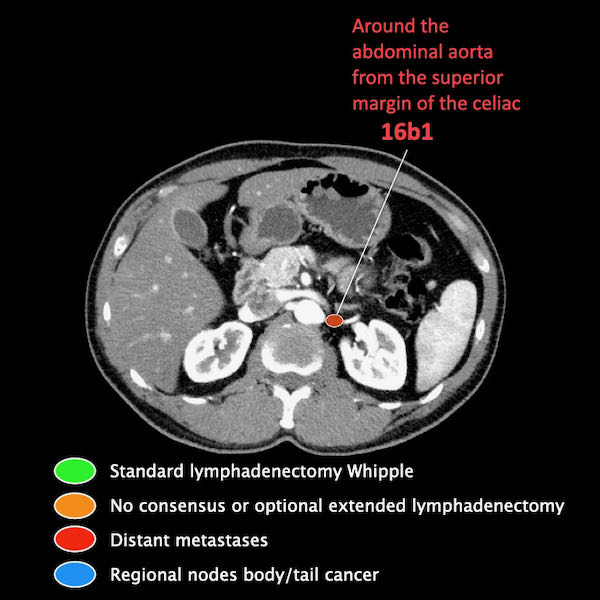

Điều quan trọng là phân biệt giữa hạch bạch huyết vùng và hạch bạch huyết ngoài vùng (di căn xa).

Các vị trí ngoài vùng chính là cạnh động mạch chủ và bên trái SMA.

Các hạch nghi ngờ ở những vị trí này cần được ghi nhận và sinh thiết.

Trong hình minh họa này, chúng tôi sử dụng các trạm hạch bạch huyết trong ung thư tụy theo đề xuất của Hội Tụy học Nhật Bản.

Các chặng hạch bạch huyết trong ung thư tụy

Các chặng hạch bạch huyết trong ung thư tụy theo đề xuất của Hội Tụy học Nhật Bản.